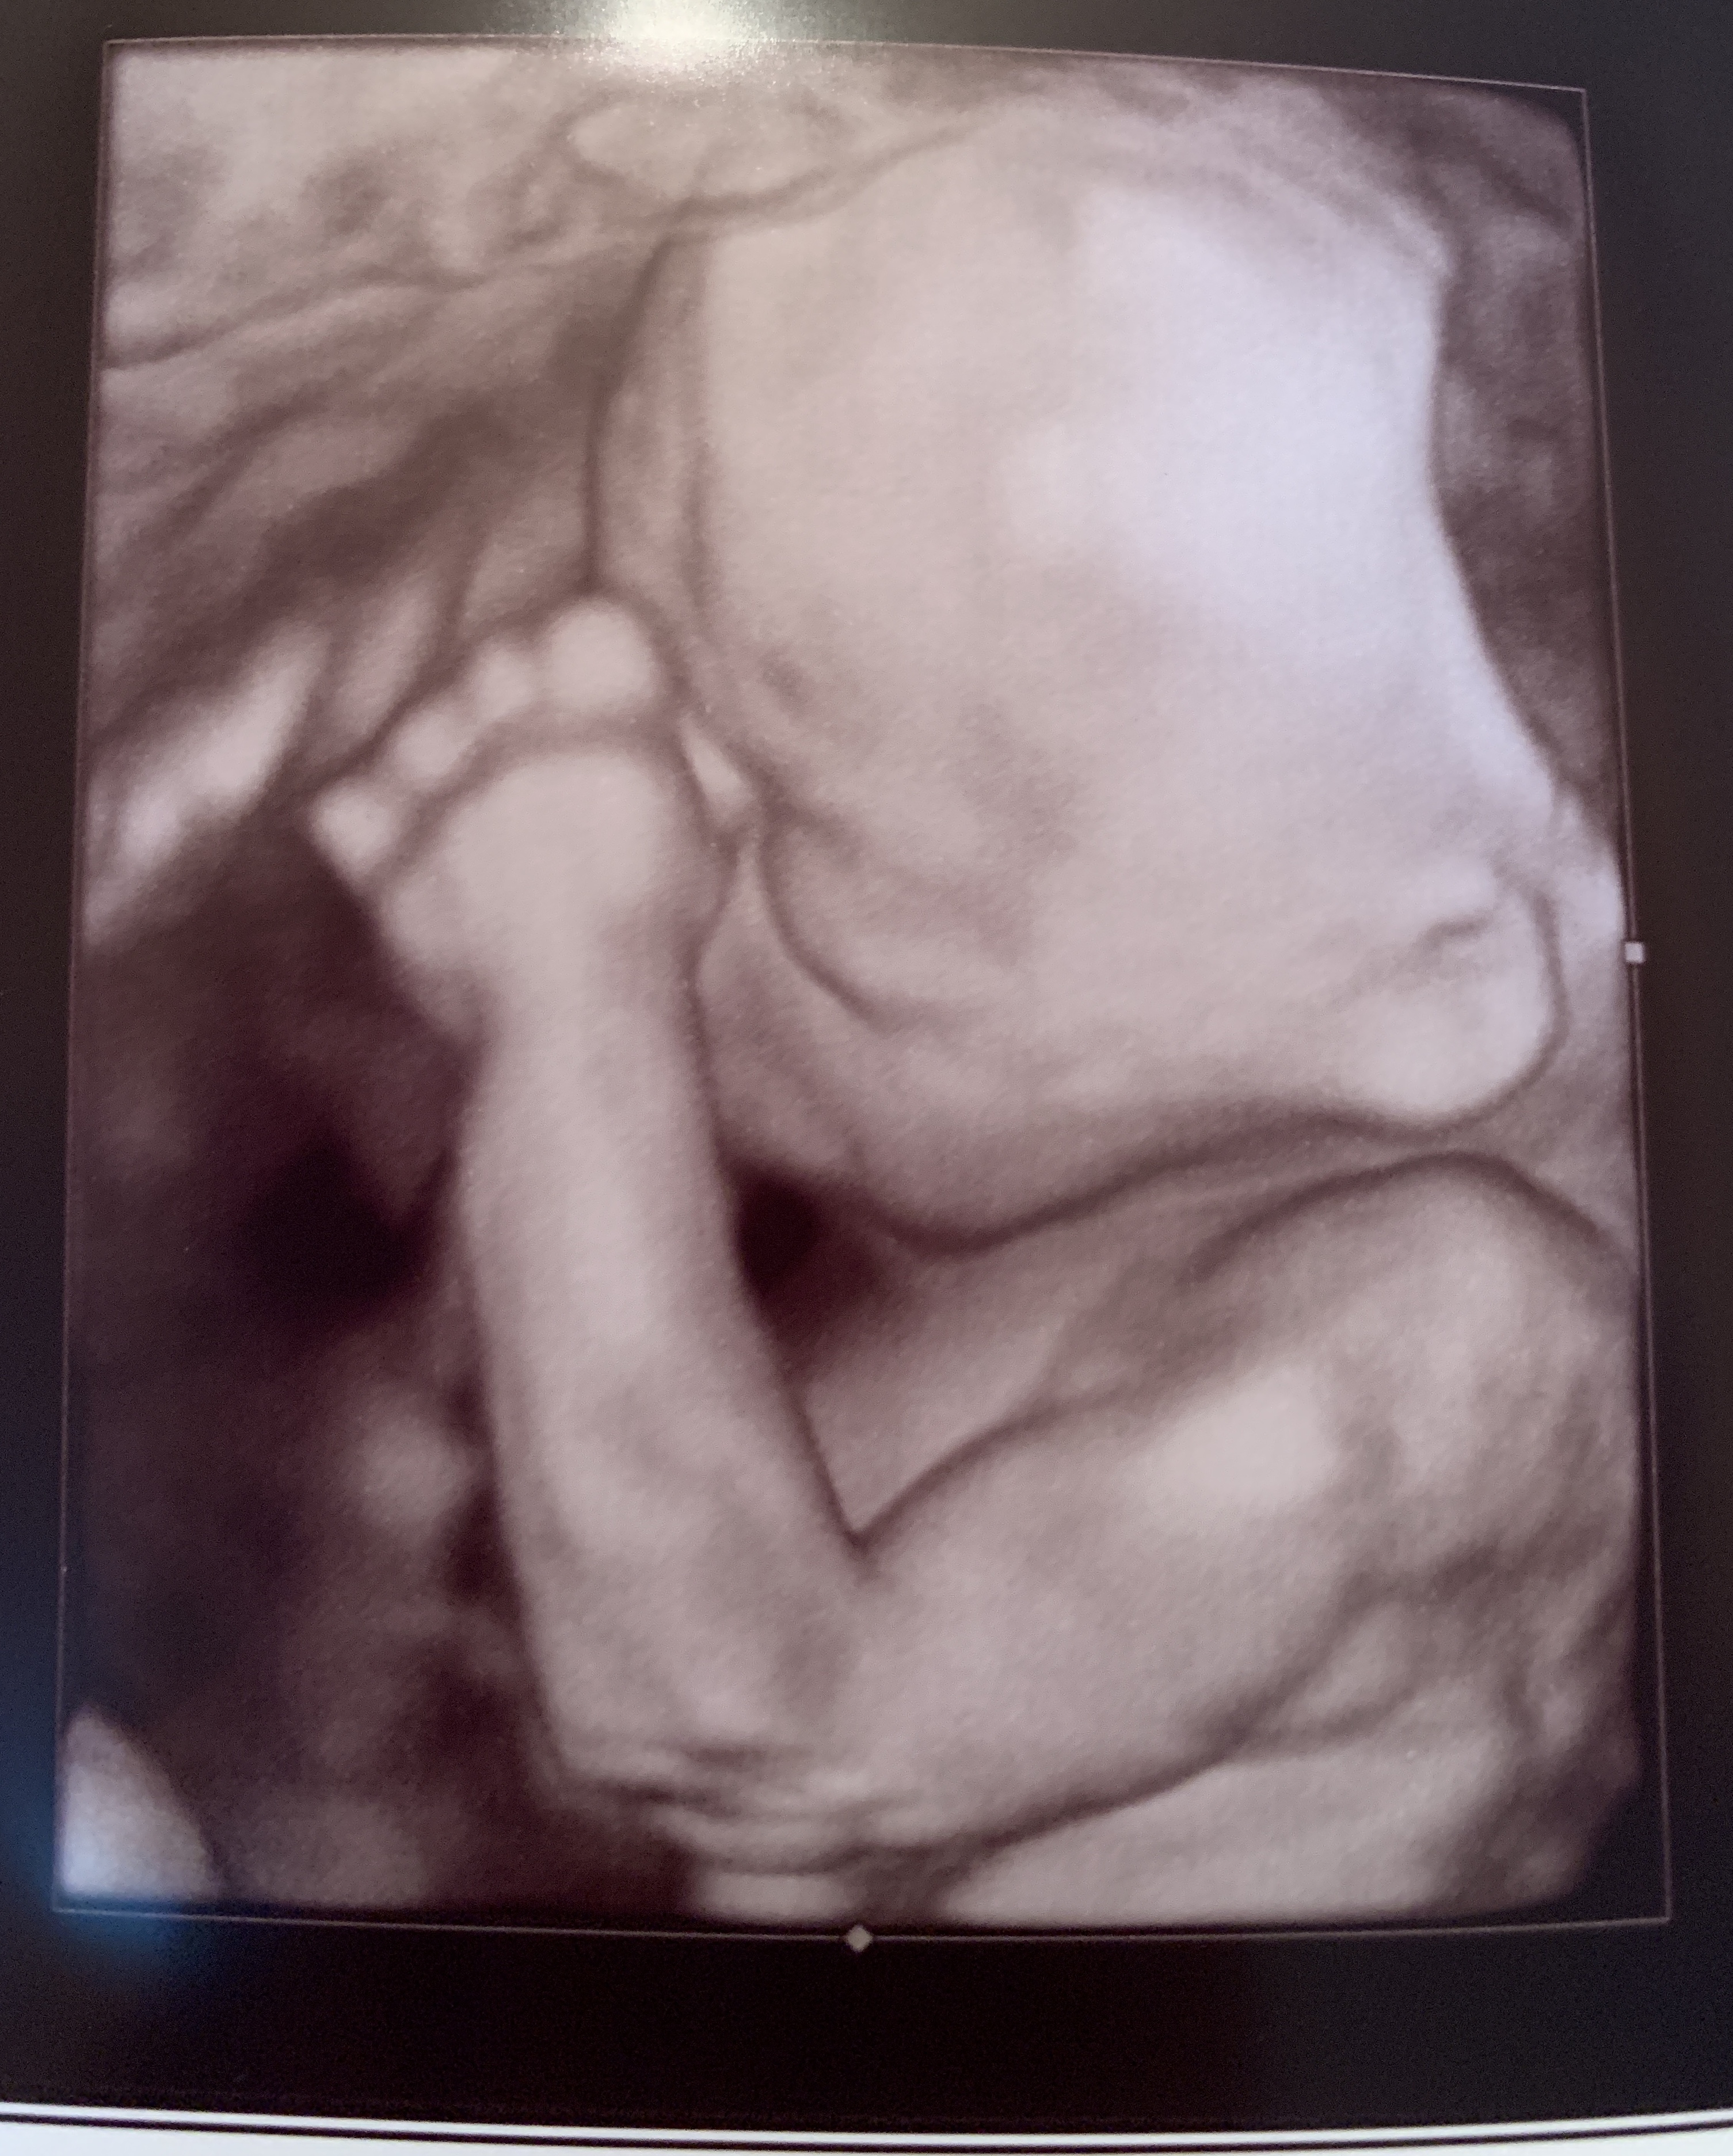

Baby girl's cute little face at exactly 28 weeks 😍